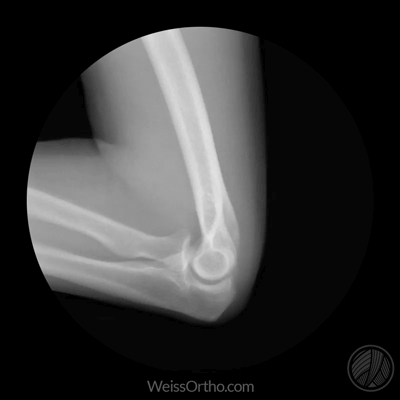

Met X-rays of Röntgenstralen kunnen we in ons lichaam kijken, maar we kennen het meestal gewoon als een foto: een stilstaand beeld van botten of gewrichten. Door fluoroscopie kunnen echter ook bewegende beelden gemaakt worden.

Ontwerper en fotograaf Cameron Drake ging aan de slag met beelden van het orthopedisch instituut van Dr. Noah Weiss in de V.S. (Weis Orthopaedics). Op zijn blog legt Drake uit hoe hij de beelden die Dr. Weiss gemaakt heeft van zijn patiënten omgezet heeft in deze gifs.